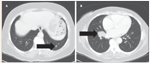

FIGURE 3

Two Examples of Pulmonary Metastases From Sarcoma

Pulmonary function tests are mandatory prior to lung surgery, and the usual guidelines for operability should be followed. Depending on age and comorbidities, cardiac testing may be appropriate as well. Removing two or three small peripheral nodules by wedge resection will have little impact on respiratory function status in most patients. A parenchyma-sparing approach is always preferred, especially given the frequency of recurrent disease in the lungs, often warranting multiple lung resections over several years. Anatomic resections, especially pneumonectomy, should be reserved for cases in which no other option for complete resection exists. Surgery is contraindicated when there is invasion of unresectable structures, or if all gross disease cannot be removed (eg, miliary disease). Ideal characteristics that allow maximal lung-sparing surgery include: unilateral and peripheral location, small tumor size, and a limited number of metastases. In contrast, large tumors, central masses, or miliary disease would be less likely to result in adequate postoperative pulmonary function (Figure 3).